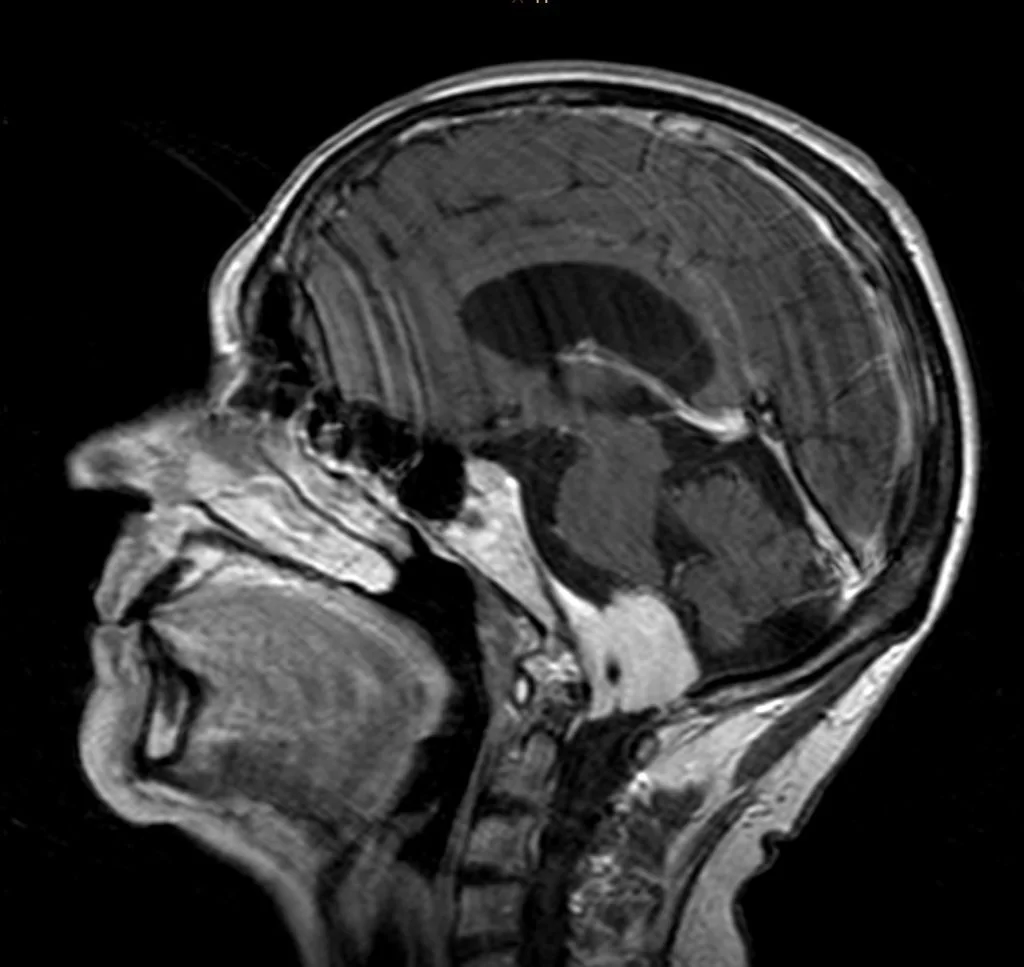

Ο προεγχειρητικός έλεγχος ανέδειξε μηνιγγίωμα της κρανιοαυχενικής συμβολής με εγκολεασμό σημαντικών αγγειακών και νευρικών δομών και επέκταση προς την αντίθετη πλευρά.

Πρόκειται για ένα εξαιρετικά απαιτητικό χειρουργείο λόγω της θέσης του όγκου. Παρόλο που πρόκειται για μια καλοήθη βλάβη (μηνιγγίωμα), ο όγκος αναπτύσσεται στο ύψος του ινιακού τρήματος και εγκολεάζει πολύ σημαντικές νευραγγειακές δομές. Επιπλέον, η μορφολογία του όγκου είναι εξαιρετικά σύνθετη, μια και επεκτείνεται έμπροσθεν του στελέχους του εγκεφάλου στην απέναντι (δεξιά) μεριά.

Χρησιμοποιήθηκε far lateral προσπέλαση. Είναι μια προσπέλαση η οποία επιτρέπει πρόσβαση τόσο στη βάση του κρανίου όσο και στην ανώτερη αυχενική μοίρα (κρανιοαυχενική συμβολή). Αφαιρέθηκε όλη η βλάβη χωρίς καμία βλάβη στις ευαίσθητες δομές.